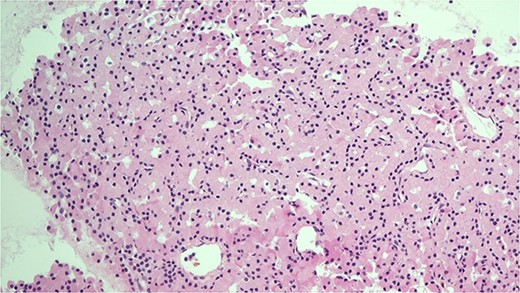

She was subsequently referred to our service for further surgical evaluation. At the time of referral, she was asymptomatic. Initial blood tests showed an elevated PTH of 1256 pg/ml (range 15–65 pg/ml), reduced adjusted calcium of 2.05 mmol/l (range 2.21–2.52 mmol/l), normal free T4 at 19.9 μg/dl (range 12–22 μg/dl), and a reduced TSH <0.01 mU/l (range 0.27–4.20 mU/l), along with a raised phosphate of 2.32 mmol/l (range 0.81–1.45 mmol/l). A CT neck showed a large left thyroid mass with a differential diagnosis of metastatic lymphadenopathy versus a parathyroid adenoma. She underwent an ultrasound and fine needle aspiration of the thyroid mass, which revealed a Thy3A lesion with no evidence of malignancy. Following further multidisciplinary team (MDT) discussion, an immunostain for PTH was performed on the EBUS TBNA, which revealed that the oncocytic cells were positive for PTH (see Figs 1 and 2). This was confirmed by a sestamibi scan, which confirmed a sestamibi-avid nodule (see Fig. 3).

H&E stain of the FNA showing oncocytic cells with abundant eosinophilic granular cytoplasm from EBUS biopsy.